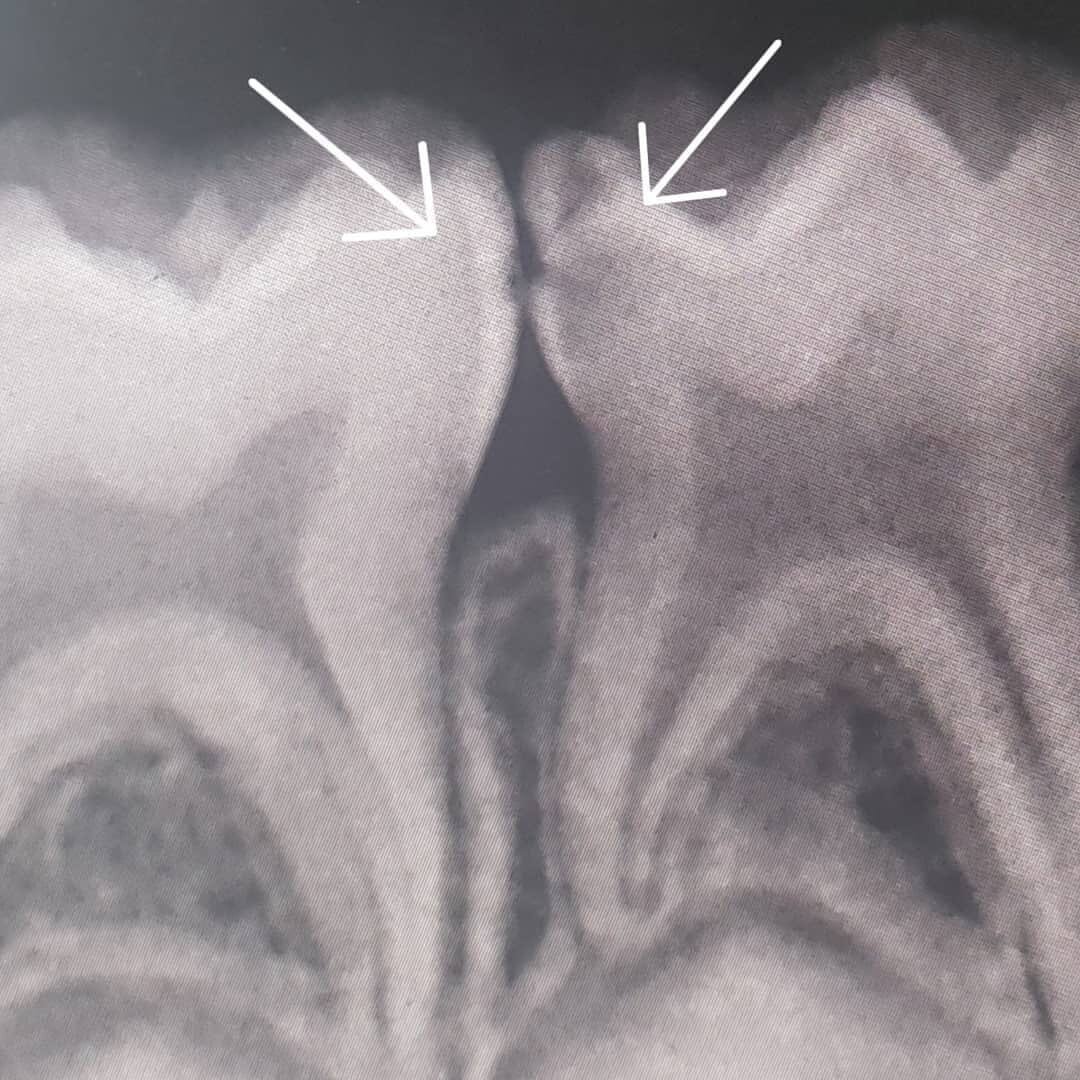

Кариес между зубами - контактный кариес.

Кариес затаился на месте контакта четвертого и пятого зуба.

✔️Для начала снимок — видим, что кариес уже «подъел» оба зуба;